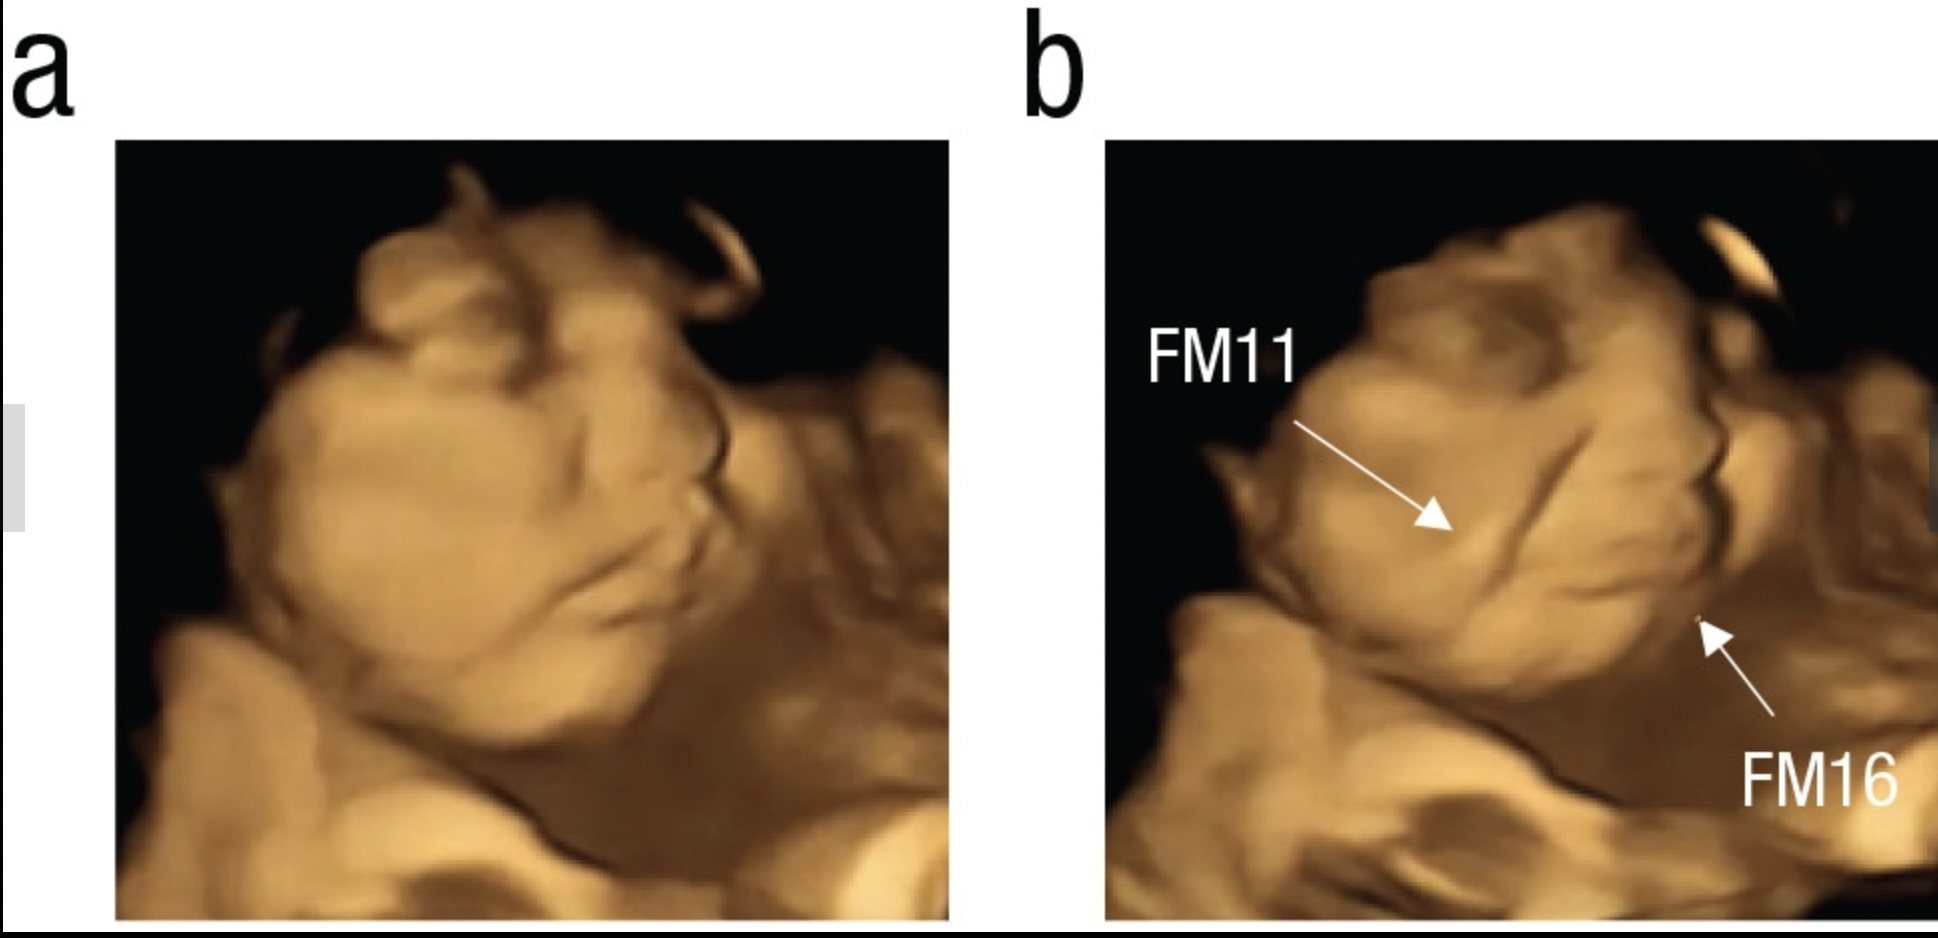

Meanwhile, babes who experienced the kale flavoring made disgusted grimaces, or “cry faces.”

If a picture’s worth a thousand words, I’d say this one just says “yuck” over and over and over.

To be fair, those scowls “might be just the muscle movements which are reacting to a bitter flavor,” Reissland noted, rather than any real showing of emotion, adding that expressions became more complex over time during gestation.